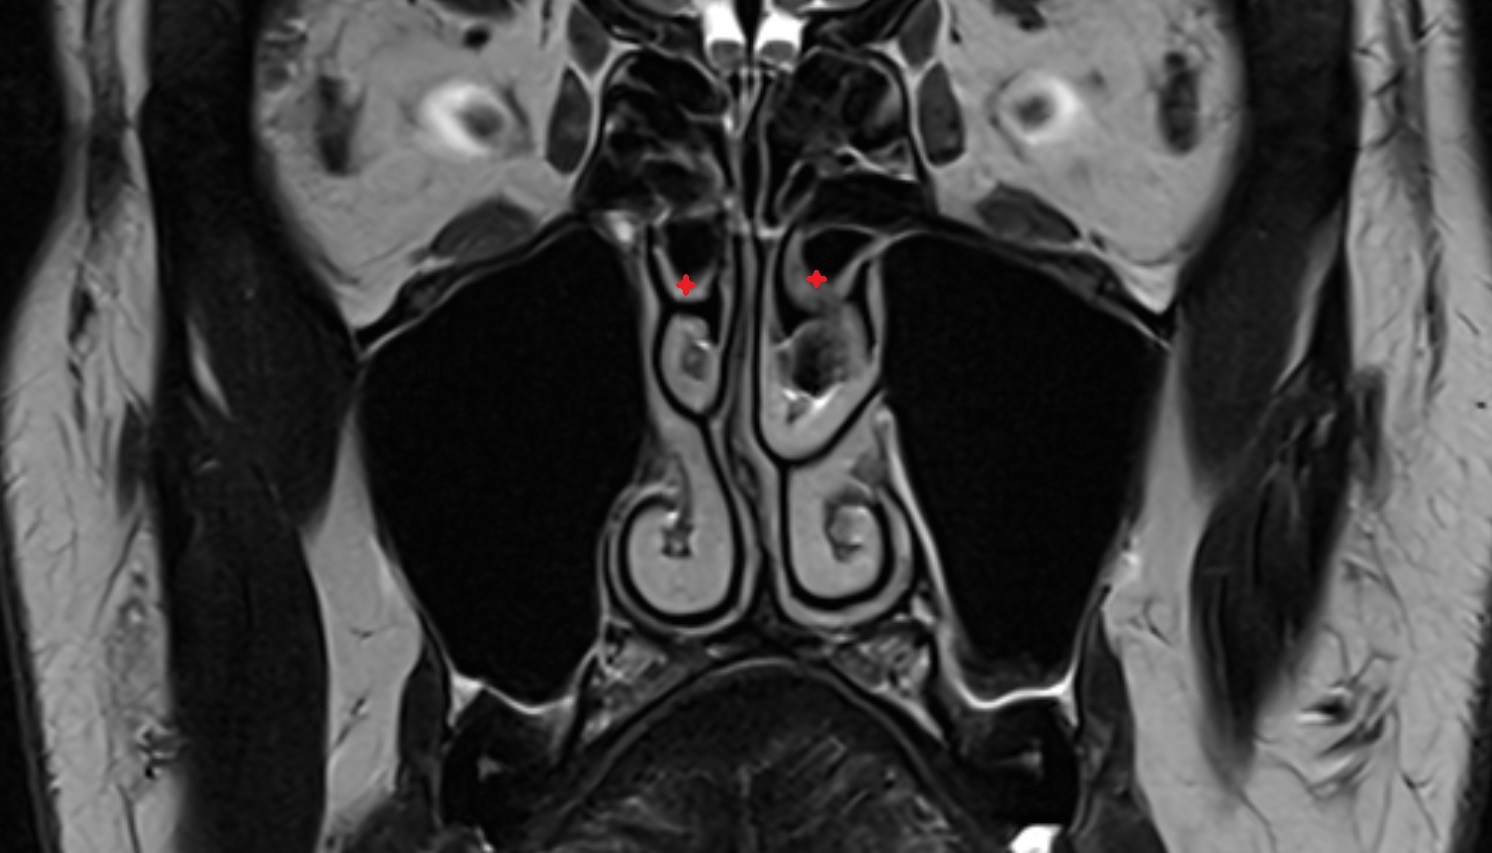

- Hippocampal head

- Head of hippocampus